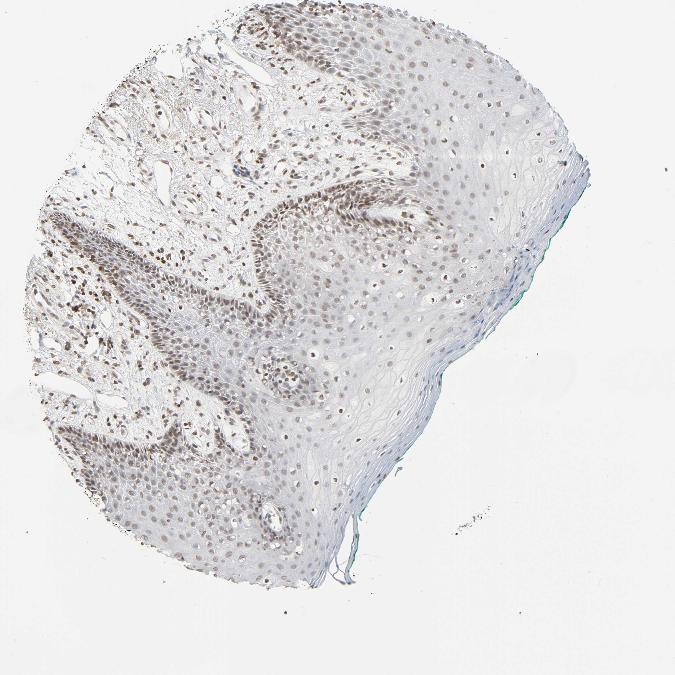

TISSUE PRIMARY DATA ORAL MUCOSA Show tissue menu

ORAL MUCOSA - Antibody stainingi

Antibody staining in the annotated cell types in the current human tissue is reported as not detected, low, medium, or high, based on conventional immunohistochemistry profiling in selected tissues. This score is based on the combination of the staining intensity and fraction of stained cells.

Each image is clickable and will lead to virtual microscopy that enables deeper exploration of all samples and also displays staining intensity scores, fraction scores and subcellular localization as well as patient and tissue information for each sample.

Antibody HPA015270Antibody CAB004038

Squamous epithelial cells LowLow